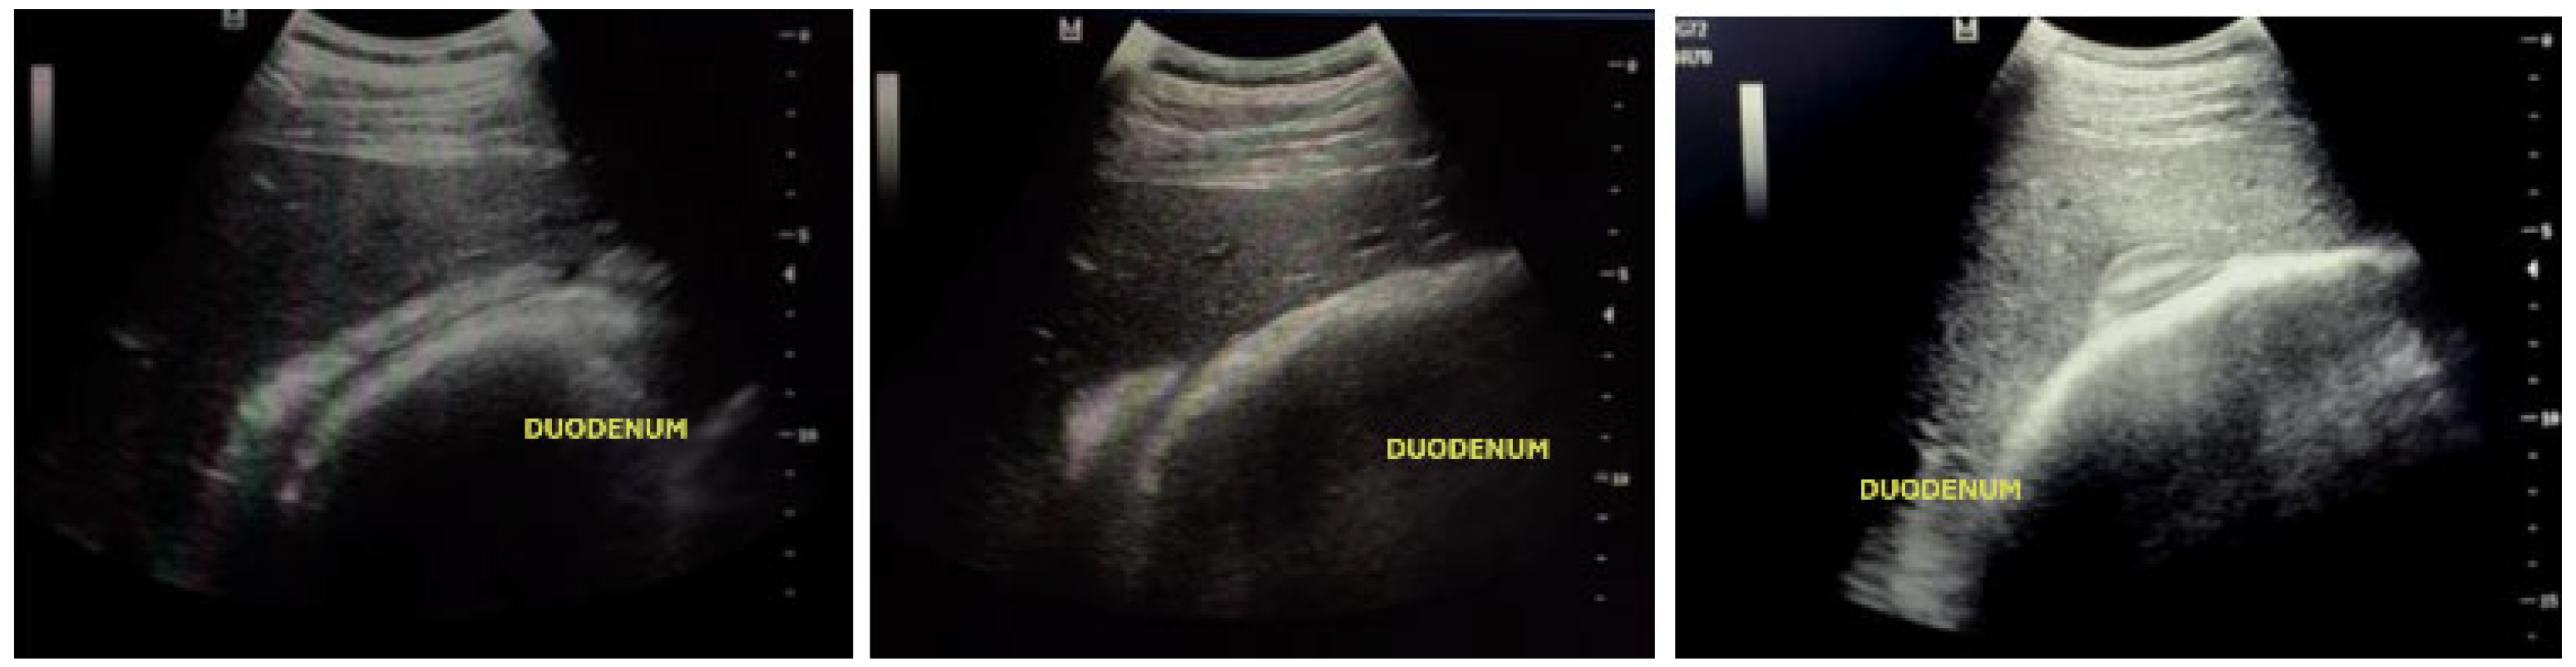

2.5.2. Ultrasound Evaluation